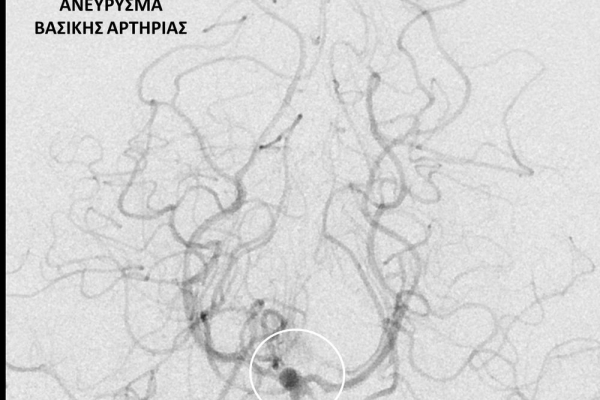

- Η ψηφιακή αγγειογραφία (DSA) αποτελεί την καλύτερη μέθοδο διάγνωσης των αγγειακών παθήσεων.Η αγγειογραφία γίνεται ως εξής: αρχικά παρακεντάται μια αρτηρία πρόσβασης, όπως η μηριαία αρτηρία στη βουβωνική περιοχή ή η βραχιόνια αρτηρία στο βραχίονα. Στη συνέχια προωθείται ένας καθετήρας προς την περιοχή του ενδιαφέροντος και γίνεται η έγχυση σκιαγραφικής ουσίας (σκιαγραφικού) με συνεχή λήψη «εικόνων» των αγγείων-στόχων.